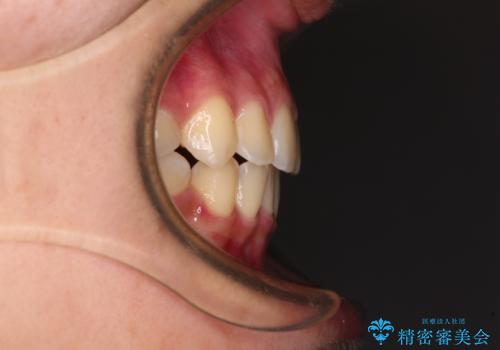

- 前歯のデコボコと八重歯を気にして来院された患者様です。

本人はあまり実感はありませんでしたが、同席されたご家族より口がすぐに開いてしまうことを指摘されていました。

口元に力の入る歯列であったため、上顎左右第一小臼歯4本を抜歯するワイヤー矯正を行うこととしました。